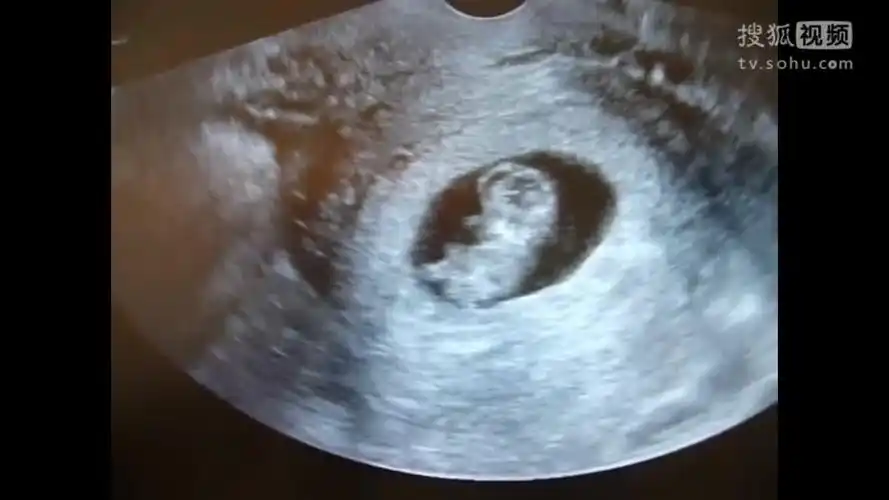

怀孕10周去做b超,惊喜的发现宝宝在里面动,连医生都说很少见-母婴亲子